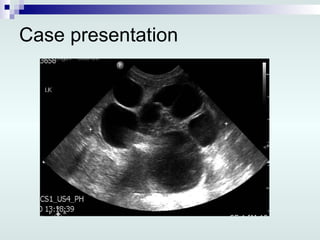

Case presentation In HSC, 3 rd  day of life: Repeated US: Lt multicystic dysplastic kidney, 6.4 cm Rt kidney smallish, 3.5 cm,  ↑ echogenicity, poor corticomedullary differentiation, mild pelvic dilatation Urinary bladder is minimally distended Minimal intraperitoneal fluid

Case presentation LK

Case presentation InHSC, 3 rd day of life: Repeated US: Lt multicystic dysplastic kidney, 6.4 cm Rt kidney smallish, 3.5 cm, ↑ echogenicity, poor corticomedullary differentiation, mild pelvic dilatation Urinary bladder is minimally distended Minimal intraperitoneal fluid